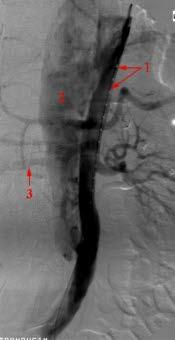

Bildet:

- Kateter i det ekte hulrommet (lumen)

- Falskt lumen

- Høyre nyrearterie som avgår fra det falske lumen